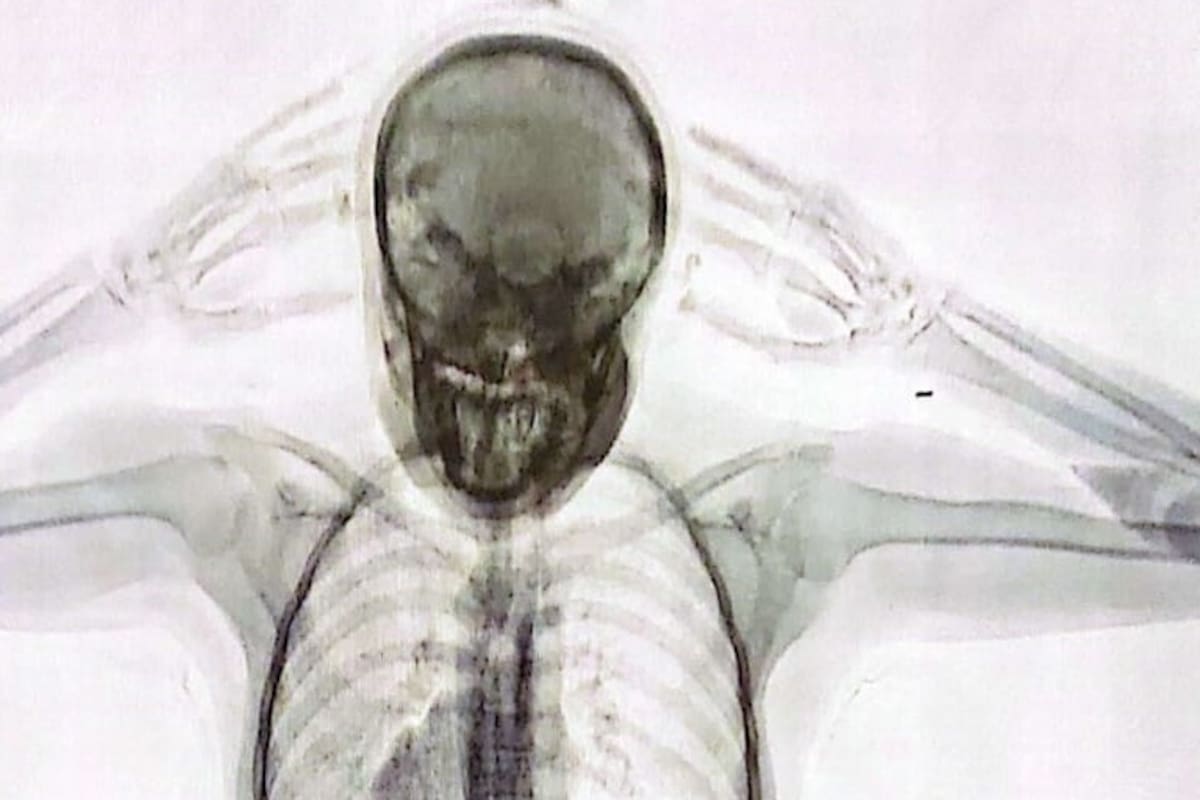

El 3 de agosto pasado se conoció la noticia de la detención de la “mula” narco cuando se hicieron públicas las imágenes captadas por un equipo de rayos X Body Scan que mostraban cómo se veían las 78 cápsulas con cocaína en el cuerpo de la joven pasajera.

La chica, que al momento de su detención estaba desempleada, estuvo internada en el Hospital Zonal General de Agudos Doctor Alberto Antranik Eurnekian, de Ezeiza, hasta que pudo evacuar todas las cápsulas con cocaína que había ingerido. Corría peligro: el estallido de uno de esos envoltorios y el contacto directo de la droga en las vísceras hubiese supuesto un altísimo riesgo de muerte. Después de eso fue trasladada a los tribunales de la Avenida de los Inmigrantes 1950, en Retiro, donde se negó a declarar ante el juez Aguinsky. En el expediente, el Ministerio Público está representado por el fiscal Emilio Guerberoff.